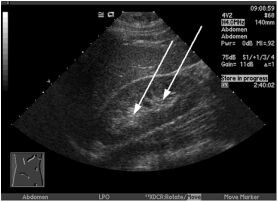

62.肝臟超音波橫向掃描時,發現一個高回音性病灶,介於右肝靜脈(right hepatic vein, RHV)與中肝靜脈(middle hepatic vein, MHV)之間(如下圖)。根據Couinaud classification的分 類,此病灶應在肝臟的那一個節段(segment)? (A)8(VIII) (B)7(VII) (C)4(IV) (D)3(III)